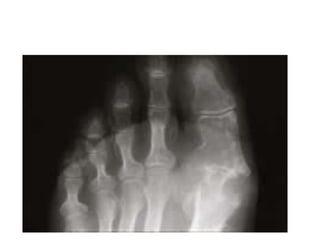

Radio: géodes arrondies ou oval,juxta-artic ou

rompant parfois la corticale osseuse avec

réaction ostéophytique imp(pieds,mains,genoux)

B/L’ arthropathie goutteuse:les dépôts intra-artic d’urate de Na entrainent des destructions ostéo- cartilagineuses des artic atteintes lors des accès aigus Clinique: Dlr mécanique avec raideur et/ou gonfl artic. Des crises aigues peuvent survenir Radio: géodes arrondies ou oval,juxta-artic ou rompant parfois la corticale osseuse avec réaction ostéophytique imp(pieds,mains,genoux)